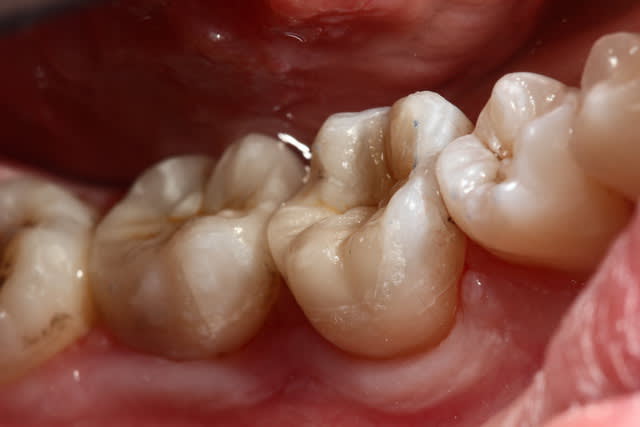

Oune plous pitite ...)))

La 16 est magnifique , le compo de la 4 également (le pan d'émail sert de point de contact , youpi)...